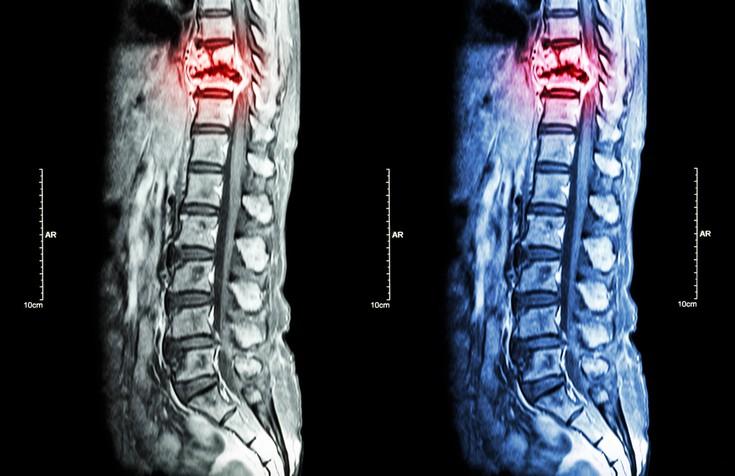

Metastasis tulang boleh didiagnosis menggunakan ujian gambar seperti:

• MRI;